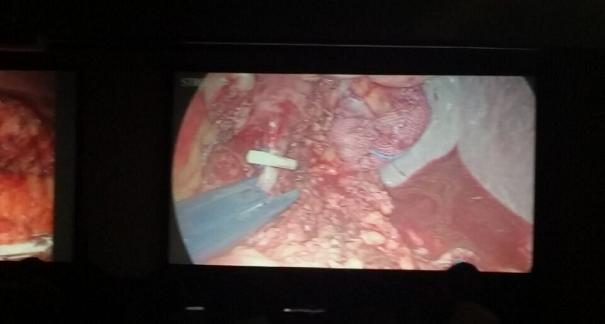

发布时间:2015-10-292015年10月23-25日,河北省医学会肝胆外科学术年会在河北省石家庄市颐园宾馆隆重召开。本次学术会议河北省医学会特邀了北京301总院的胡明根教授、天津第一中心医院的张雅敏教授、山西医大医院的赵浩亮、河北医科大学第二医院刘建华教授等国内知名专家参会。参加会议的医院达100余家,近300名肝胆外科的临床专家和一线医生们亲临会场,在此进行广泛的学术交流。25号全天会议安排了五台手术视频演示,全体参会人员进行观摩,并实时提问,进行手术交流。演示手术包括腹腔镜胰、十二指肠切除术、腹腔镜左、右半肝切除术、腹腔镜门脉高压症的治疗、两镜或三镜联合胆石症的治疗、开腹胰、十二指肠切除术、手术演示中多次使用了我公司产品速丰(可吸收止血结扎夹),产品使用满意度受到专家们的一致好评。